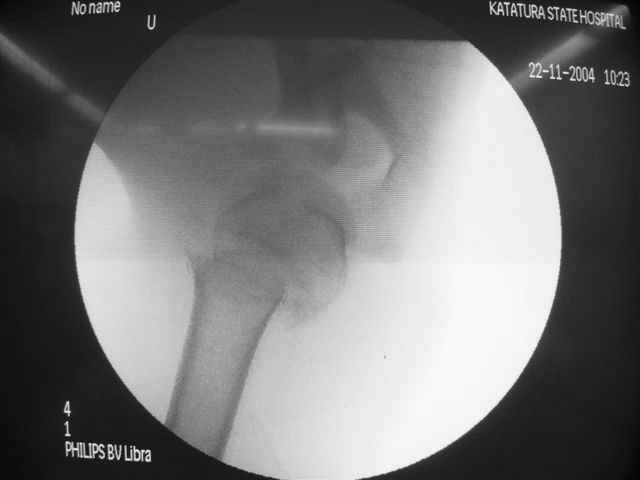

Коллеги, Больной прооперирован вчера. 19 летний пациент с переломом шейки плеча. Закрытая репозиция и чрескожная фиксация спицами под контролем ЭОПа ( техника проф. Лазарева)

Интраоперационный контроль на стабильность фиксации - сомнений в стабильности фиксации не возникло. Послеоперационный контроль сегодня......

Необходимость послеоперационного Рг контроля..... Больной запланирован на повторную манипуляцию и транспозицию спиц Евгений И Чекашкин